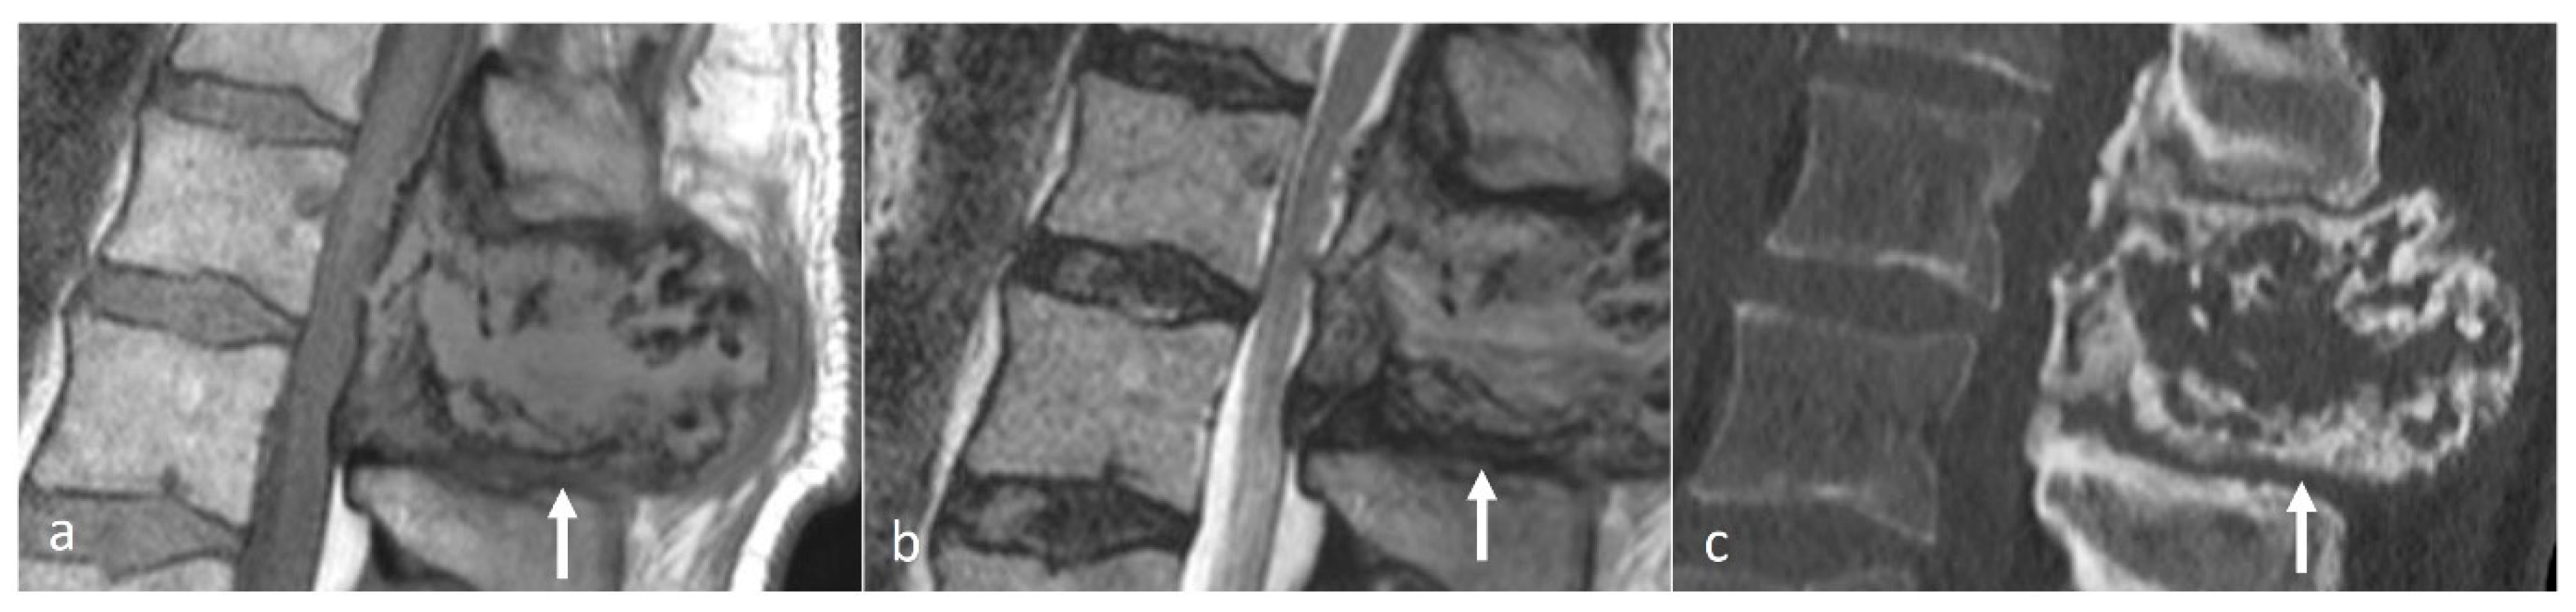

Figure 6.

Sagittal T1 (a), T2 (b) and CT (c) images of a sclerotic myelomatous deposit involving a thoracic spinous process (white arrows). While myeloma typically tends to present as lytic lesions, occasionally they can be expansile and sclerotic as seen here.